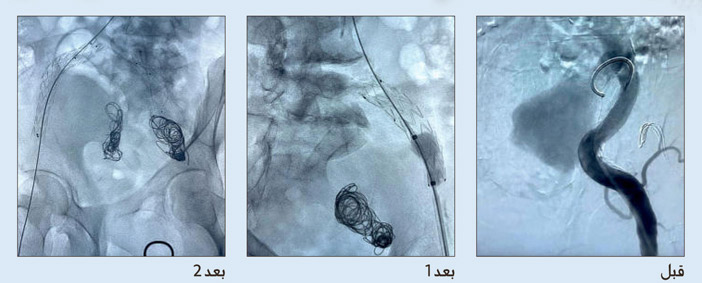

قام فريق جراحة الأوعية بإجراء عملية جراحية دقيقة بواسطة القسطرة لمريض يبلغ من العمر 70 عاماً يعاني من السكر والضغط والفشل الكلوي ولديه توسع كبير في شرايين الحوض الجهة اليمنى والجهة اليسرى، حيث بلغ حجم التوسع 7 سم مما قد يؤدي الى انفجار الشريان بالتالي موت المريض وأجريت العملية بالقسطرة نظراً لصعوبة الحالة من الناحية الجراحية عن طريق شريان الفخذ بواسطة ادخال انبوب صغير جداً، ومن ثم إقفال التوسع بواسطة مواد معدنية تسمى كويلز وبعدها عمل دعامة مغطاة لتخفيف او اغلاق جريان الدم في هذا الانتفاخ ثم اغلاق مكان القسطرة بواسطة جهاز يسمى بروكلايد، حيث لا تحتاج لعملية فتح أو مشرط جراحي.

وقد أجريت العملية على مرحلتين وذلك لتخفيف نسبة قصور الدورة الدموية في أعضاء الحوض، حيث اجريت العملية الاولى قبل شهر ثم أخرج المريض من المستشفى وهو بصحة جيدة ثم المرحلة الثانية حيث تم إجراء القسطرة التداخلية واغلاق التوسع الشرياني وتجنب العمليات الجراحية.

العملية الأولى والثانية تمت تحت التخدير الموضعي وفي غرفة القسطرة دون الحاجة الى تخدير كامل او عمليات جراحية معقدة، وتعتبر هذه العملية من العمليات المتقدمة والحديثة، وكذلك من الحالات النادرة جداً وبنفس الوقت خطيرة اذا تركت لانها قد تؤدي الى انفجار شرايين الحوض والوفاة لا قدر الله، وخرج المريض معافى بصحة جيدة بفضل الله تعالى والفريق الطبي بقسم الأوعية الدموية بإشراف استشاريين سعوديين وتوفر الكفاءات الطبية واحدث الاجهزة وفق معايير عالمية.